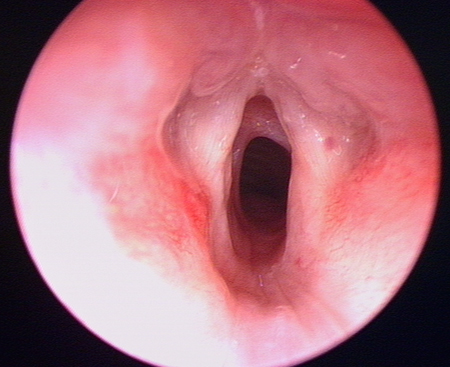

Laryngomalacia

Typical example of laryngomalacia

From the personal teaching collection of Simone J. Boardman, MBBS, FRACS (OHNS) and C. Martin Bailey, BSc, FRCS, FRCSEd